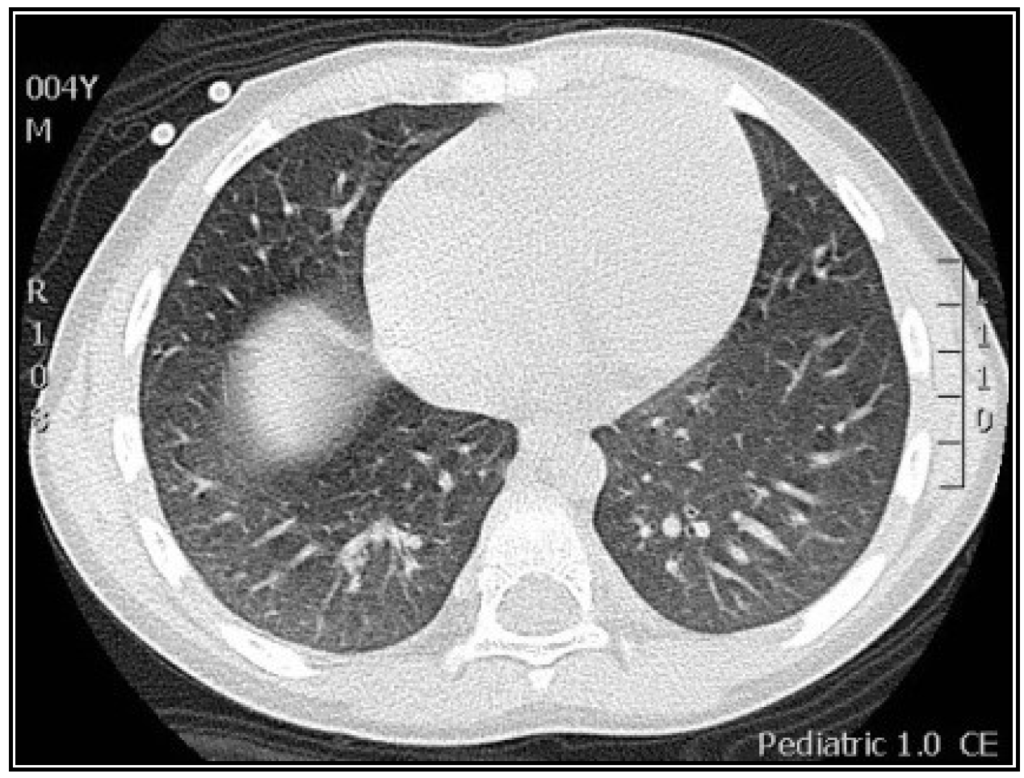

| Radiological variables | |

| Abnormal lung images, n (%) | 15 (100) |

| Ground-glass opacity, n (%) | 12 (80) |

| Consolidation, n (%) | 12 (80) |

| Atelectasis, n (%) | 6 (40) |

| Air trapping, n (%) | 5 (33) |

| Nodular pattern, n (%) | 3 (20) |

| Reticular pattern, n (%) | 1 (6) |

| Tree-in-bud pattern, n (%) | 1 (6) |

3.2. Radiological Findings in CMV Lung Infection